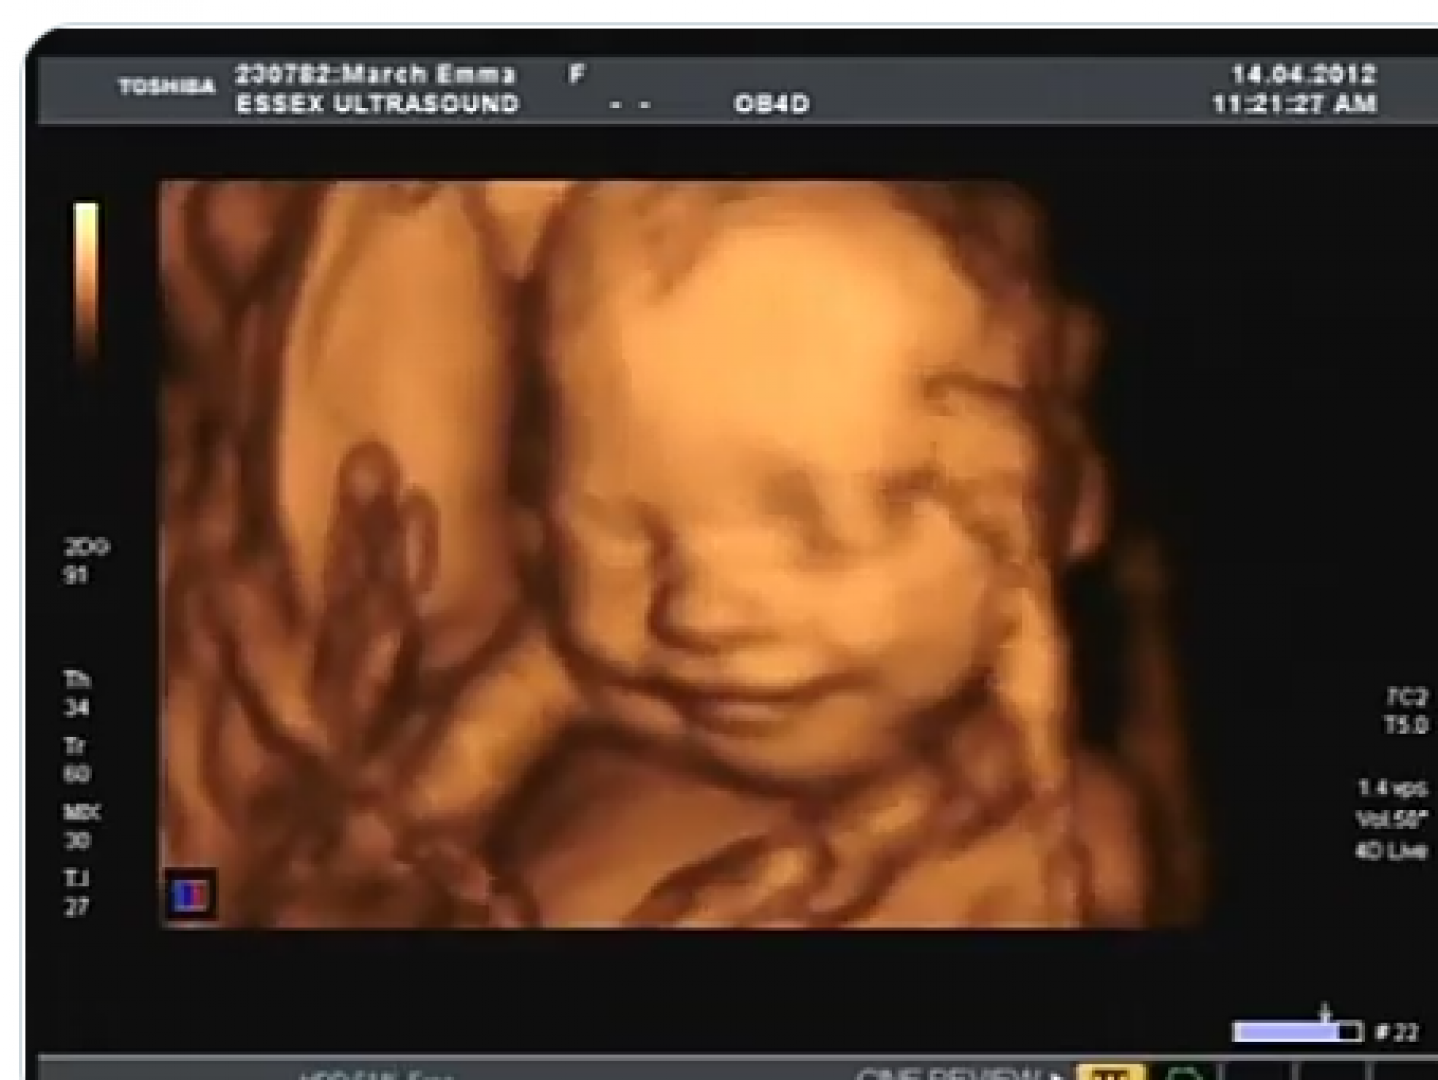

لذلك في حالة عدم ملاحظة حركة الجنين من الجدير على الحامل أن تقوم بزيارة طبيب متخصص من أجل إجراء الفحص باستخدام الأشعة فوق الصوتية للتأكد من صحة الجنين وقياس معدل ضربات القلب، وحجمه ومعدل النمو وتدفق الدم إليه.